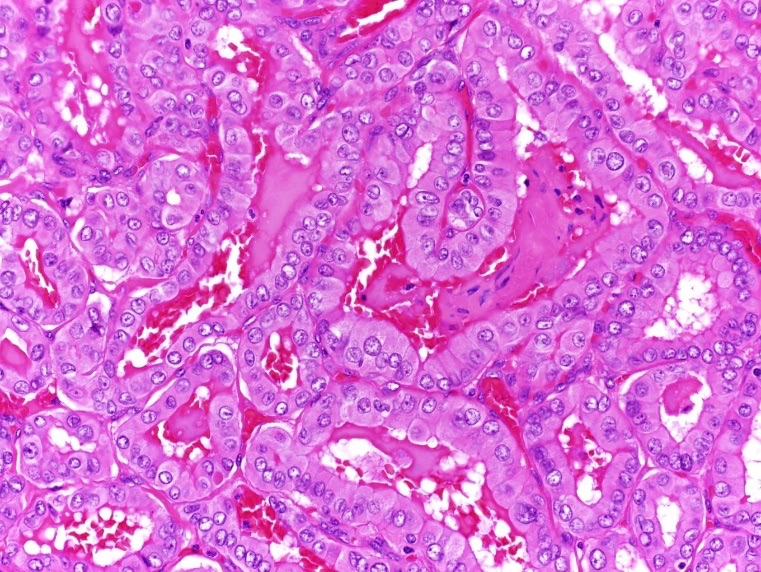

The patient underwent a total thyroidectomy without lymph node dissection. Pathologically, the right thyroid lobe was benign, with no evidence of active malignancy. A 7-mm nodule in the isthmus showed papillary thyroid microcarcinoma with 25% tall-cell morphology and evidence of focal extrathyroidal extension without angioinvasion or lymphatic invasion (Figures 7 and 8).

Figure 7. Hematoxylin-eosin stained pathology of papillary thyroid carcinoma in the isthmus nodule, intermediate-power view (×200) showing tall tumor cells with abundant eosinophilic cytoplasm (aggressive variant of papillary thyroid carcinoma) with focal extrathyroidal extension.

Figure 8. Hematoxylin-eosin stain, high-power view (×400) showing the nuclear features of the papillary thyroid cancer.